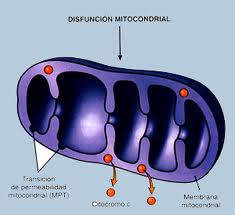

lo que sugiere que ambas enfermedades pueden proceder de mecanismos de plegamiento similares. Una presentación de los caminos patogénicos comunes asociados con estos trastornos, incluyendo mecanismos de muerte celular, la producción de especies reactivas de oxígeno, la disfunción mitocondrial y anomalías vasculares, servirán como un punto de inicio para posteriores estudios.